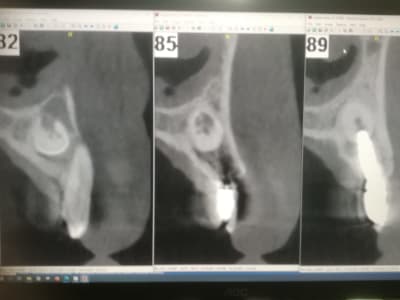

là par exemple on est très très proche de la racine... :

3b4kdca6bxig2am518lqpvuf47g3 - Eugenol

@ Hokusai

Là aussi on est très proche. Trop d'ailleurs.

Ca s'est mal terminé.

Je me souviens d'une conf à l'ADF d'un praticien qui affirmait avec beaucoup d'aplomb qu'il n'y avait aucun problème à transfixer des racines. Depuis j'ai vu ce cas, et j'ai un peu plus de doutes.